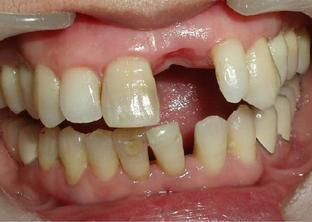

“牙龈线下移”,即牙龈萎缩,指的是牙根部位的牙龈退缩,将牙根暴露出来。牙龈萎缩不可小觑,如不重视,严重者会出现牙齿松动,甚至脱落。

一旦出现牙龈萎缩,表现为:牙龈红肿,刷牙出血;牙齿变长,牙缝变大;牙根开始暴露;遇到冷热酸甜,牙齿敏感;牙齿松动。

温馨提醒:牙龈萎缩是导致牙齿缺失的重要原因,所以患有牙周病的朋友要注意控制病情发展,防止牙龈继续萎缩,避免牙齿松动甚至脱落。